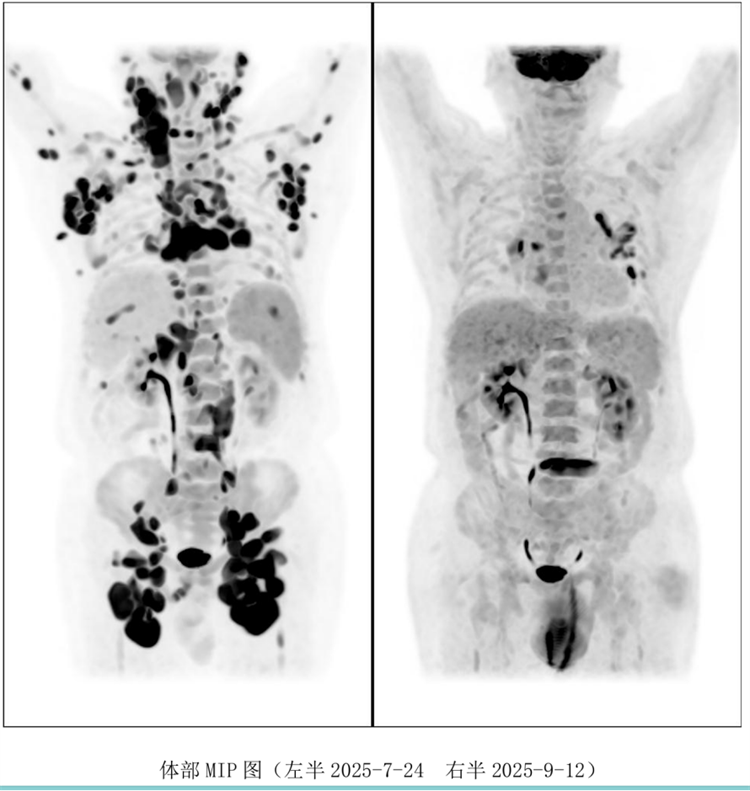

病例汇报环节由我院淋巴瘤科张薇医生带来了三例精彩纷呈的难治复发弥漫大B淋巴瘤CAR-T治疗的病例。

病例过程跌宕起伏,从桥接治疗到靶点的选择,并发症的处理都极具代表性。张医生详尽分享了患者在治疗过程中的挑战、决策依据以及CAR-T细胞治疗后的惊人缓解与转归,充分展示了CAR-T技术为晚期患者带来的突破性生存希望。